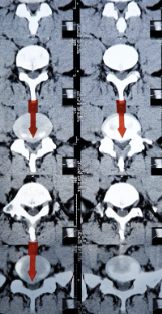

추간판 탈출증 증상 원인 치료방법 등 추간판 탈출증에 대해 정리해드리도록 하겠습니다. 추간판 탈출증은 척추 뼈 사이에 있는 젤리 같은 추간판이 손상되어 신경을 압박하거나 자극하는 질환입니다. 이 질환은 통증, 저림감, 무감각, 근력 저하 등의 증상을 유발할 수 있으며, 특히 요추 부위에서 가장 흔하게 발생합니다. 추간판 탈출증의 원인은 다양하지만, 대부분은 척추의 퇴행성 변화나 반복적인 외상으로 인해 발생합니다. 이 글에서는 추간판 탈출증의 증상과 치료 방법에 대해 알아보겠습니다.

추간판 탈출증의 증상은 탈출된 디스크의 위치와 크기, 그리고 압박되는 신경의 종류에 따라 다르게 나타납니다. 가장 흔한 증상은 다음과 같습니다.

- 통증: 추간판 탈출증에서 가장 흔하고 주된 증상입니다. 통증은 보통 척추 주변에서 시작되어 다리나 팔로 뻗쳐 나갑니다. 통증은 척추를 움직일 때나 기침, 재채기 등으로 악화될 수 있습니다. 특히 요추 추간판 탈출증에서는 좌골신경통이라고 하는 다리의 바깥쪽과 발뒤꿈치로 내려가는 통증이 특징적입니다.

- 저림감/찌림감: 추간판이 신경을 자극하면, 그 신경이 공급하는 부위에 저림감이나 찌림감을 느낄 수 있습니다. 이러한 감각 이상은 주로 다리나 발에서 느껴지며, 편안한 자세를 찾기 어렵게 만들 수 있습니다.

- 무감각: 추간판이 신경을 압박하면, 그 신경이 공급하는 부위에 감각이 없어질 수 있습니다. 이는 심각한 증상으로, 일상 생활에 큰 영향을 미칠 수 있습니다.

- 근력 감소: 추간판이 운동신경을 압박하면, 그 신경이 제어하는 근육의 기능이 저하될 수 있습니다. 이는 근력 저하나 근육 손상으로 나타날 수 있으며, 특히 다리의 근육에서 뚜렷합니다.